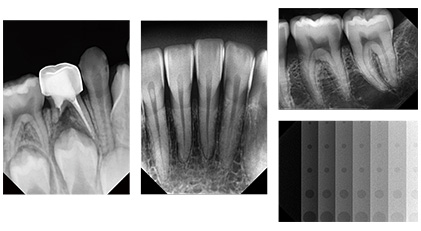

EzSensor Classic为准确的诊断和治疗计划提供优质影像。 EzSensor Classic通过高灵敏度传感器技术为您提供稳定的影像质量。在各种曝光设置情况下,X射线源仍然可以拍摄可诊断的一致图像。 由于高对比度,它可以详细查看不同密度(不透明度)的口腔内部情况。此外,图像中还可以容易区分近端携带物。